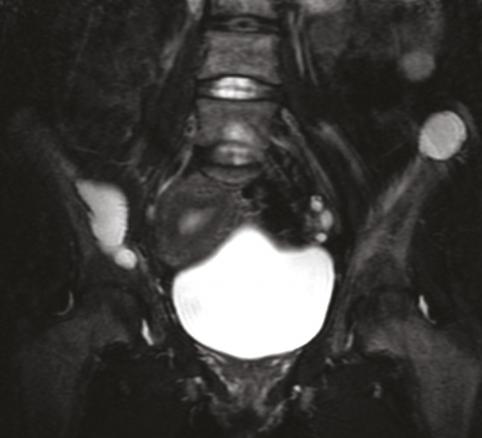

Cette femme de 31 ans sans antécédents était adressée pour des douleurs pelviennes, un syndrome polyuro-polydipsique et une altération de l’état général. Le bilan biologique montrait une hypercalcémie, une hypophosphorémie, une hypovitaminose D et une hyperparathormonémie. La tomodensitométrie (TDM) [fig. 1 ] et l’imagerie par résonance magnétique (IRM) [fig. 2 ] du pelvis révélaient un aspect ostéolytique diffus avec des nodules tumoraux des ailes iliaques. La scintigraphie et l’examen histologique de trois volumineuses glandes parathyroïdes permettait de retenir le diagnostic d’hyperplasie parathyroïdienne primaire. La biopsie osseuse confirmait le diagnostic de tumeurs brunes osseuses associées à l’hyperparathyroïdie. L’évolution était favorable sous traitement symptomatique et antalgique.

Ces tumeurs sont devenues rares du fait d’un diagnostic plus précoce de l’hyperparathyroïdie. Leur aspect radiologique est celui d’une ostéolyse non spécifique.2 Les principaux diagnostics différentiels sont les métastases osseuses et les lésions myélomateuses.